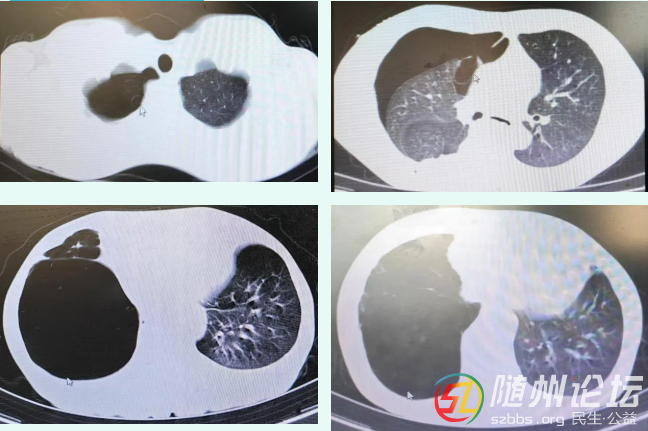

以下便是近期部分肺大皰患者術(shù)前影像表現(xiàn),讓我們撥云見霧,一睹真容。

注:圖中箭頭所指均為肺大泡